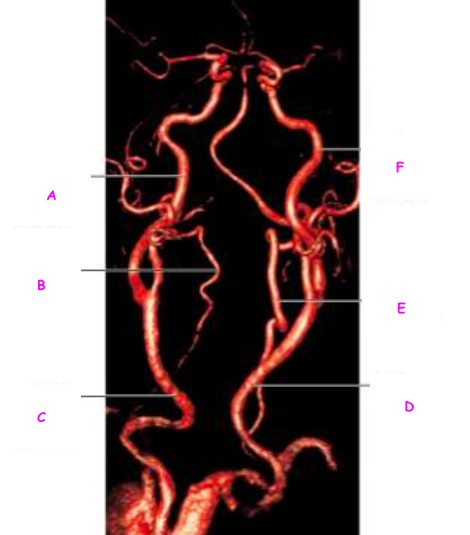

Q

Which of the following is the right common carotid artery

A

B

C

D

E

F

23

Which of the following is the left internal carotid artery

24

Which of the following is the left vertebral artery